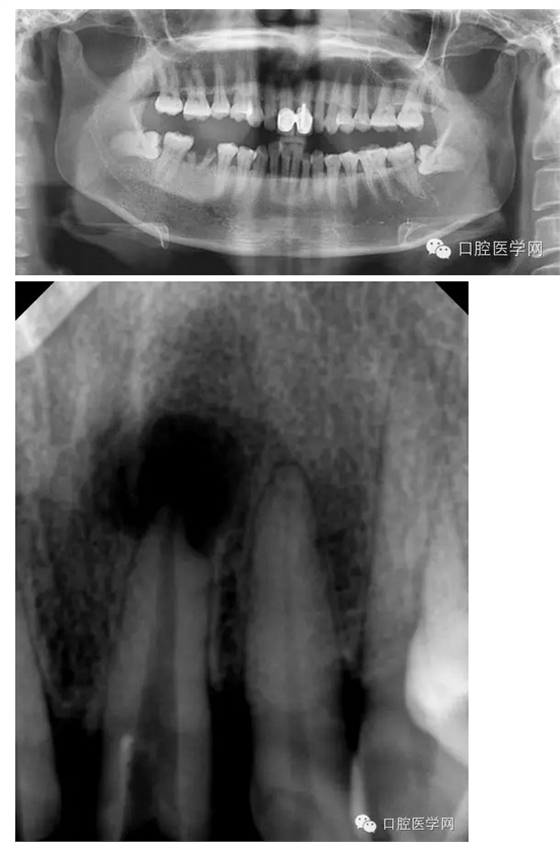

首頁各類病例 左上1根尖膿腫患者

左上1根尖膿腫患者

主訴:上前牙腫痛兩日

現(xiàn)病史:上中切牙疼痛兩日,逐漸加重,自覺唇部腫脹,今來我院求治。

既往史:五年前曾在其他診所鑲過兩顆門牙,具體不詳。

檢查:21相對應(yīng)的前庭溝隆起,粘膜紅腫,有波動感,門診(+),叩(++)。

輔助檢查:21x線示根周有大面積陰影

診斷:21急性根尖周炎

治療方案:建議拆除牙冠,21行根管治療,樁核、全冠修復(fù)